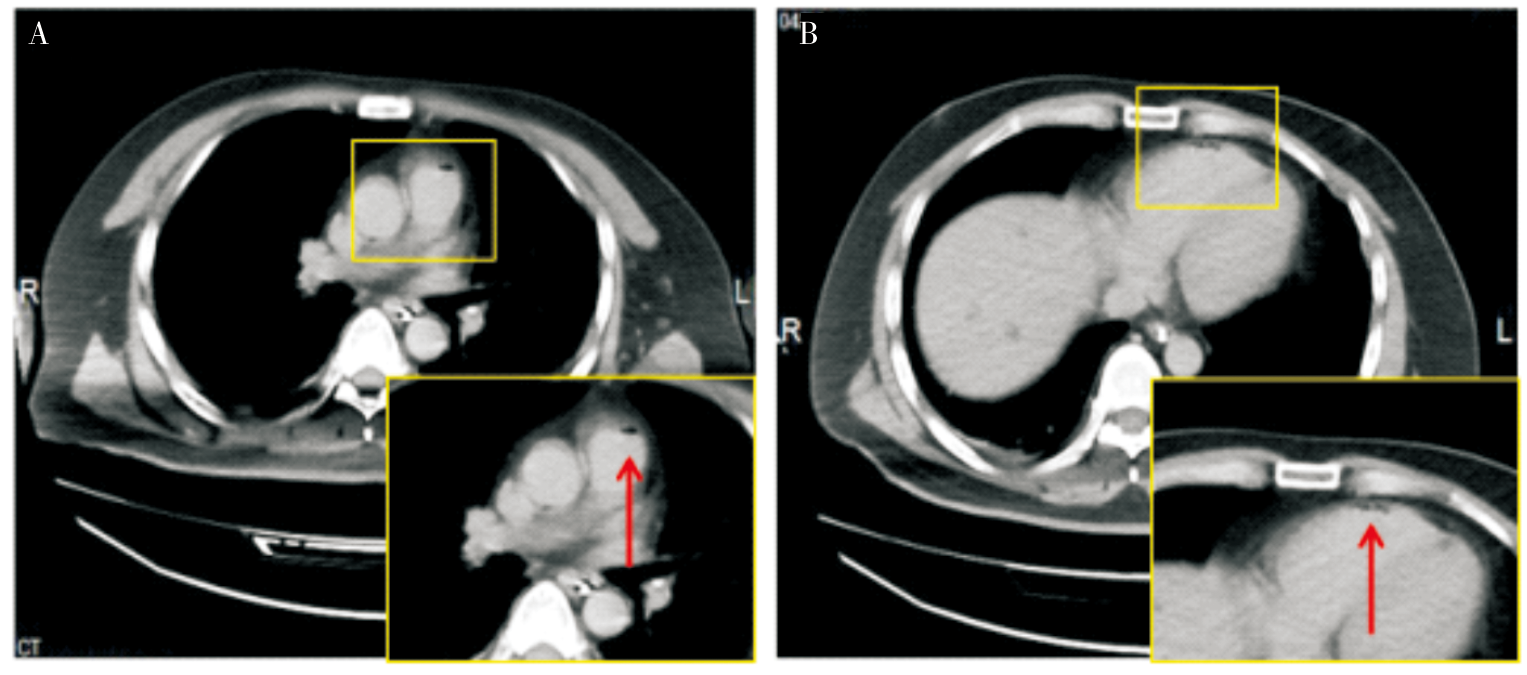

| [25] | LIU Y, CHEN J, WANG H, et al. Systemic air embolism during ERCP: a case report and focus on identification and management[J]. Jpn J Gastroenterol Hepatol, 2021, 18(6):1-4. |